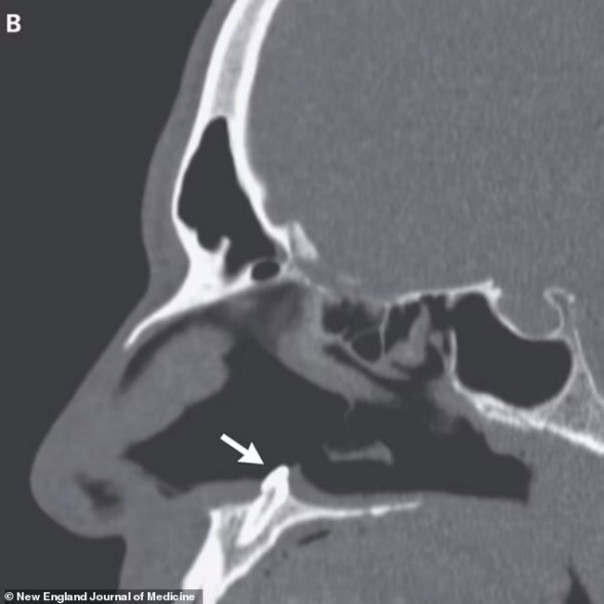

Врачи провели мужчине риноскопию и нашли в одной из ноздрей плотную белую массу, которая не вызывала болевых ощущений. Оказалось, что это эктопический зуб длиной 14 миллиметров, который вырос не там, где ему следовало бы.

Мужчине провели операцию и удалили зуб, вскоре проблемы с дыханием прекратились.